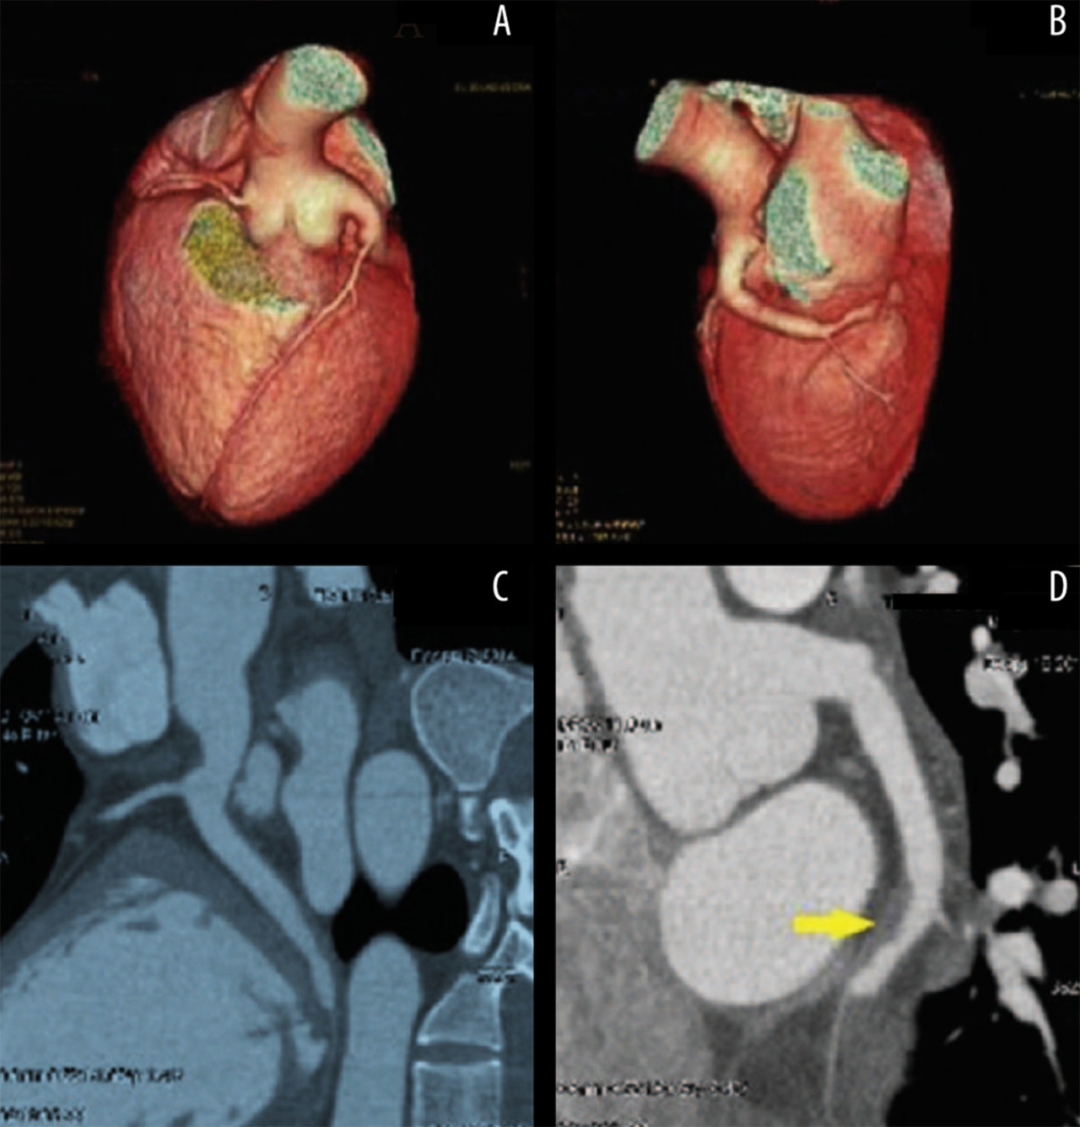

冠脉扩张症定义为弥漫性扩张累及范围超过其长度的1/3以上,且扩张段的直径是相邻正常段直径的1.5倍以上。这与冠脉瘤的定义不同,后者是指冠脉某段直径超过相邻正常冠脉段直径的1.5倍,且累及范围占总长度的1/3以下。冠脉扩张症有时会导致急性冠脉综合征。研究显示,扩张段存在明显的血流缓慢现象,可能导致缺血和血栓形成。近期,天津医大总医院李永乐教授团队在《American Journal of Case Reports》报道了一份特殊病例“Recurrent Acute Myocardial Infarction in a Patient with Severe Coronary Artery Ectasia Followed Up for 10 Years: Implications of Anticoagulant Therapy”,报告了一例在9年间因同一冠脉扩张病变部位局部血栓形成导致再发心肌梗死的病例,并讨论了长期抗凝治疗的有效性。